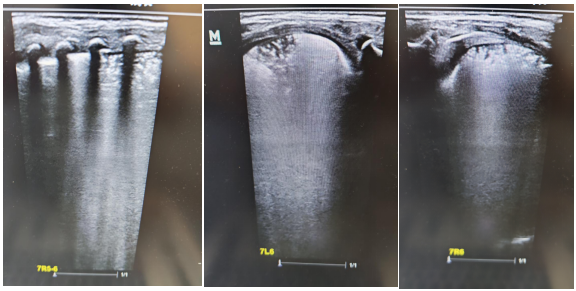

術前肺部超聲及CT均提示雙肺實變明顯

超聲顯示肺實變基本吸收